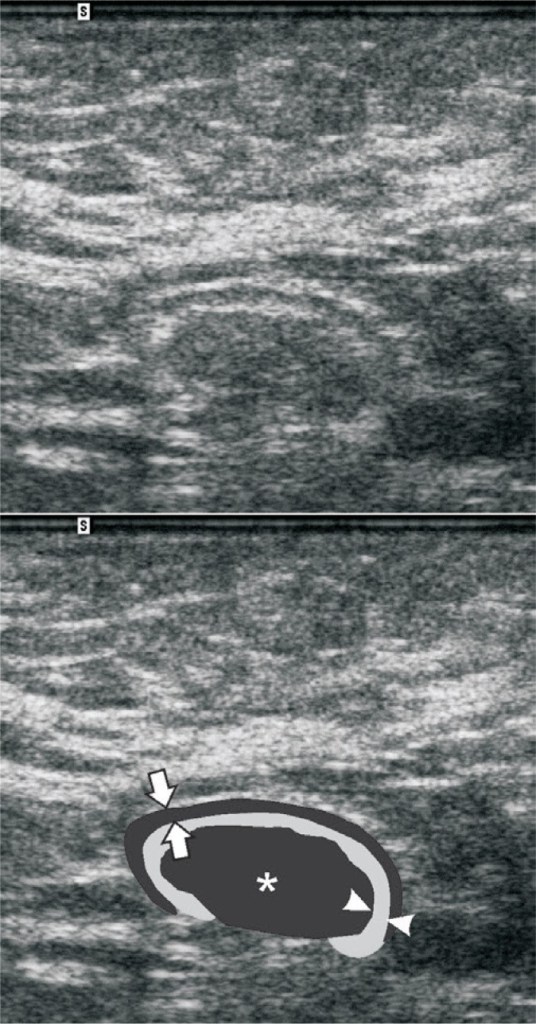

A bedside US was obtained of the area which showed:

A typical lymph node should appear as a hypoechoic structure with an echogenic hilum:

Some characteristics of malignant lymph nodes are eccentric hypertrophy, lack of an echogenic hilum, large size, cystic or necrotic areas, ill defined margins, and heterogenous appearance:

Normal lymph nodes, benign lymphadenopathy, and malignant lymphadenopathy all can mimic other structures on ultrasonography which is why the emergency physician should be aware of their appearance. Be aware of the anatomical distribution and location of lymph nodes to avoid misclassifying a lymph node as a blood vessel. Also obtain images in both longitudinal and transverse positions. Blood vessels will look very different in longitudinal and transverse positions however lymph nodes will retain their round appearance. If there is something that appears to be a fluid collection, search the surrounding area for other “fluid collections” as lymph nodes tend to appear in chains. Be aware that some fluid collections may contain separations and heterogenous material and can mimic lymph nodes. If in doubt, obtain a radiology based study.

Lymph node mimicking fluid collection:

Lymph node mimicking clot:

The ultrasound obtained in our patient showed epitrochlear lymphadenopathy. A radiology based study was obtained and was interpreted by radiology as unable to rule out malignancy and they recommended a future lymph node biopsy.